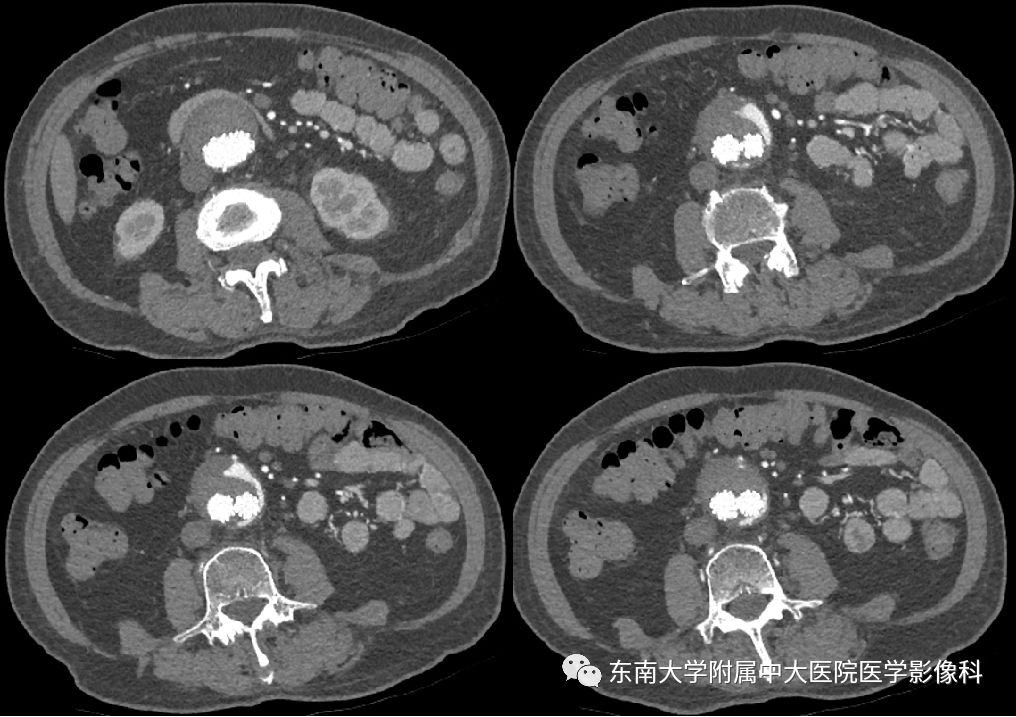

腹主动脉瘤

腹主动脉瘤的随访丨哪些ct征象提示其不稳定性

腹主动脉瘤的随访,哪些ct征象提示其不稳定性?